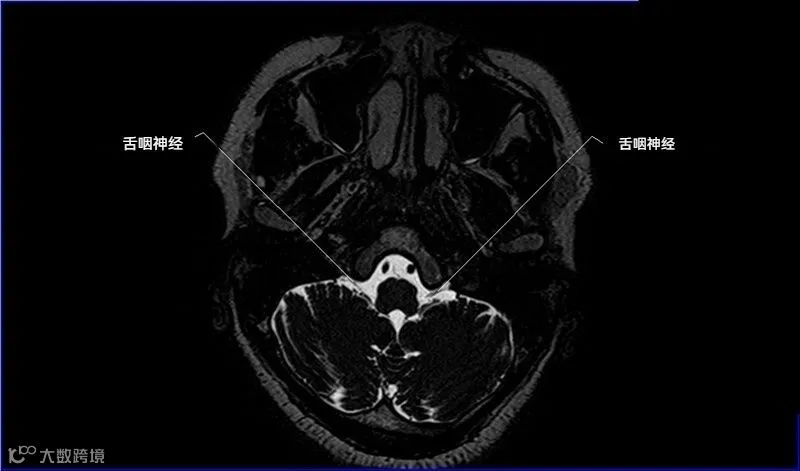

十二对脑神经口诀

一嗅二视三动眼,四滑五叉六外展,

七面八听九舌咽,迷走及副舌下全。